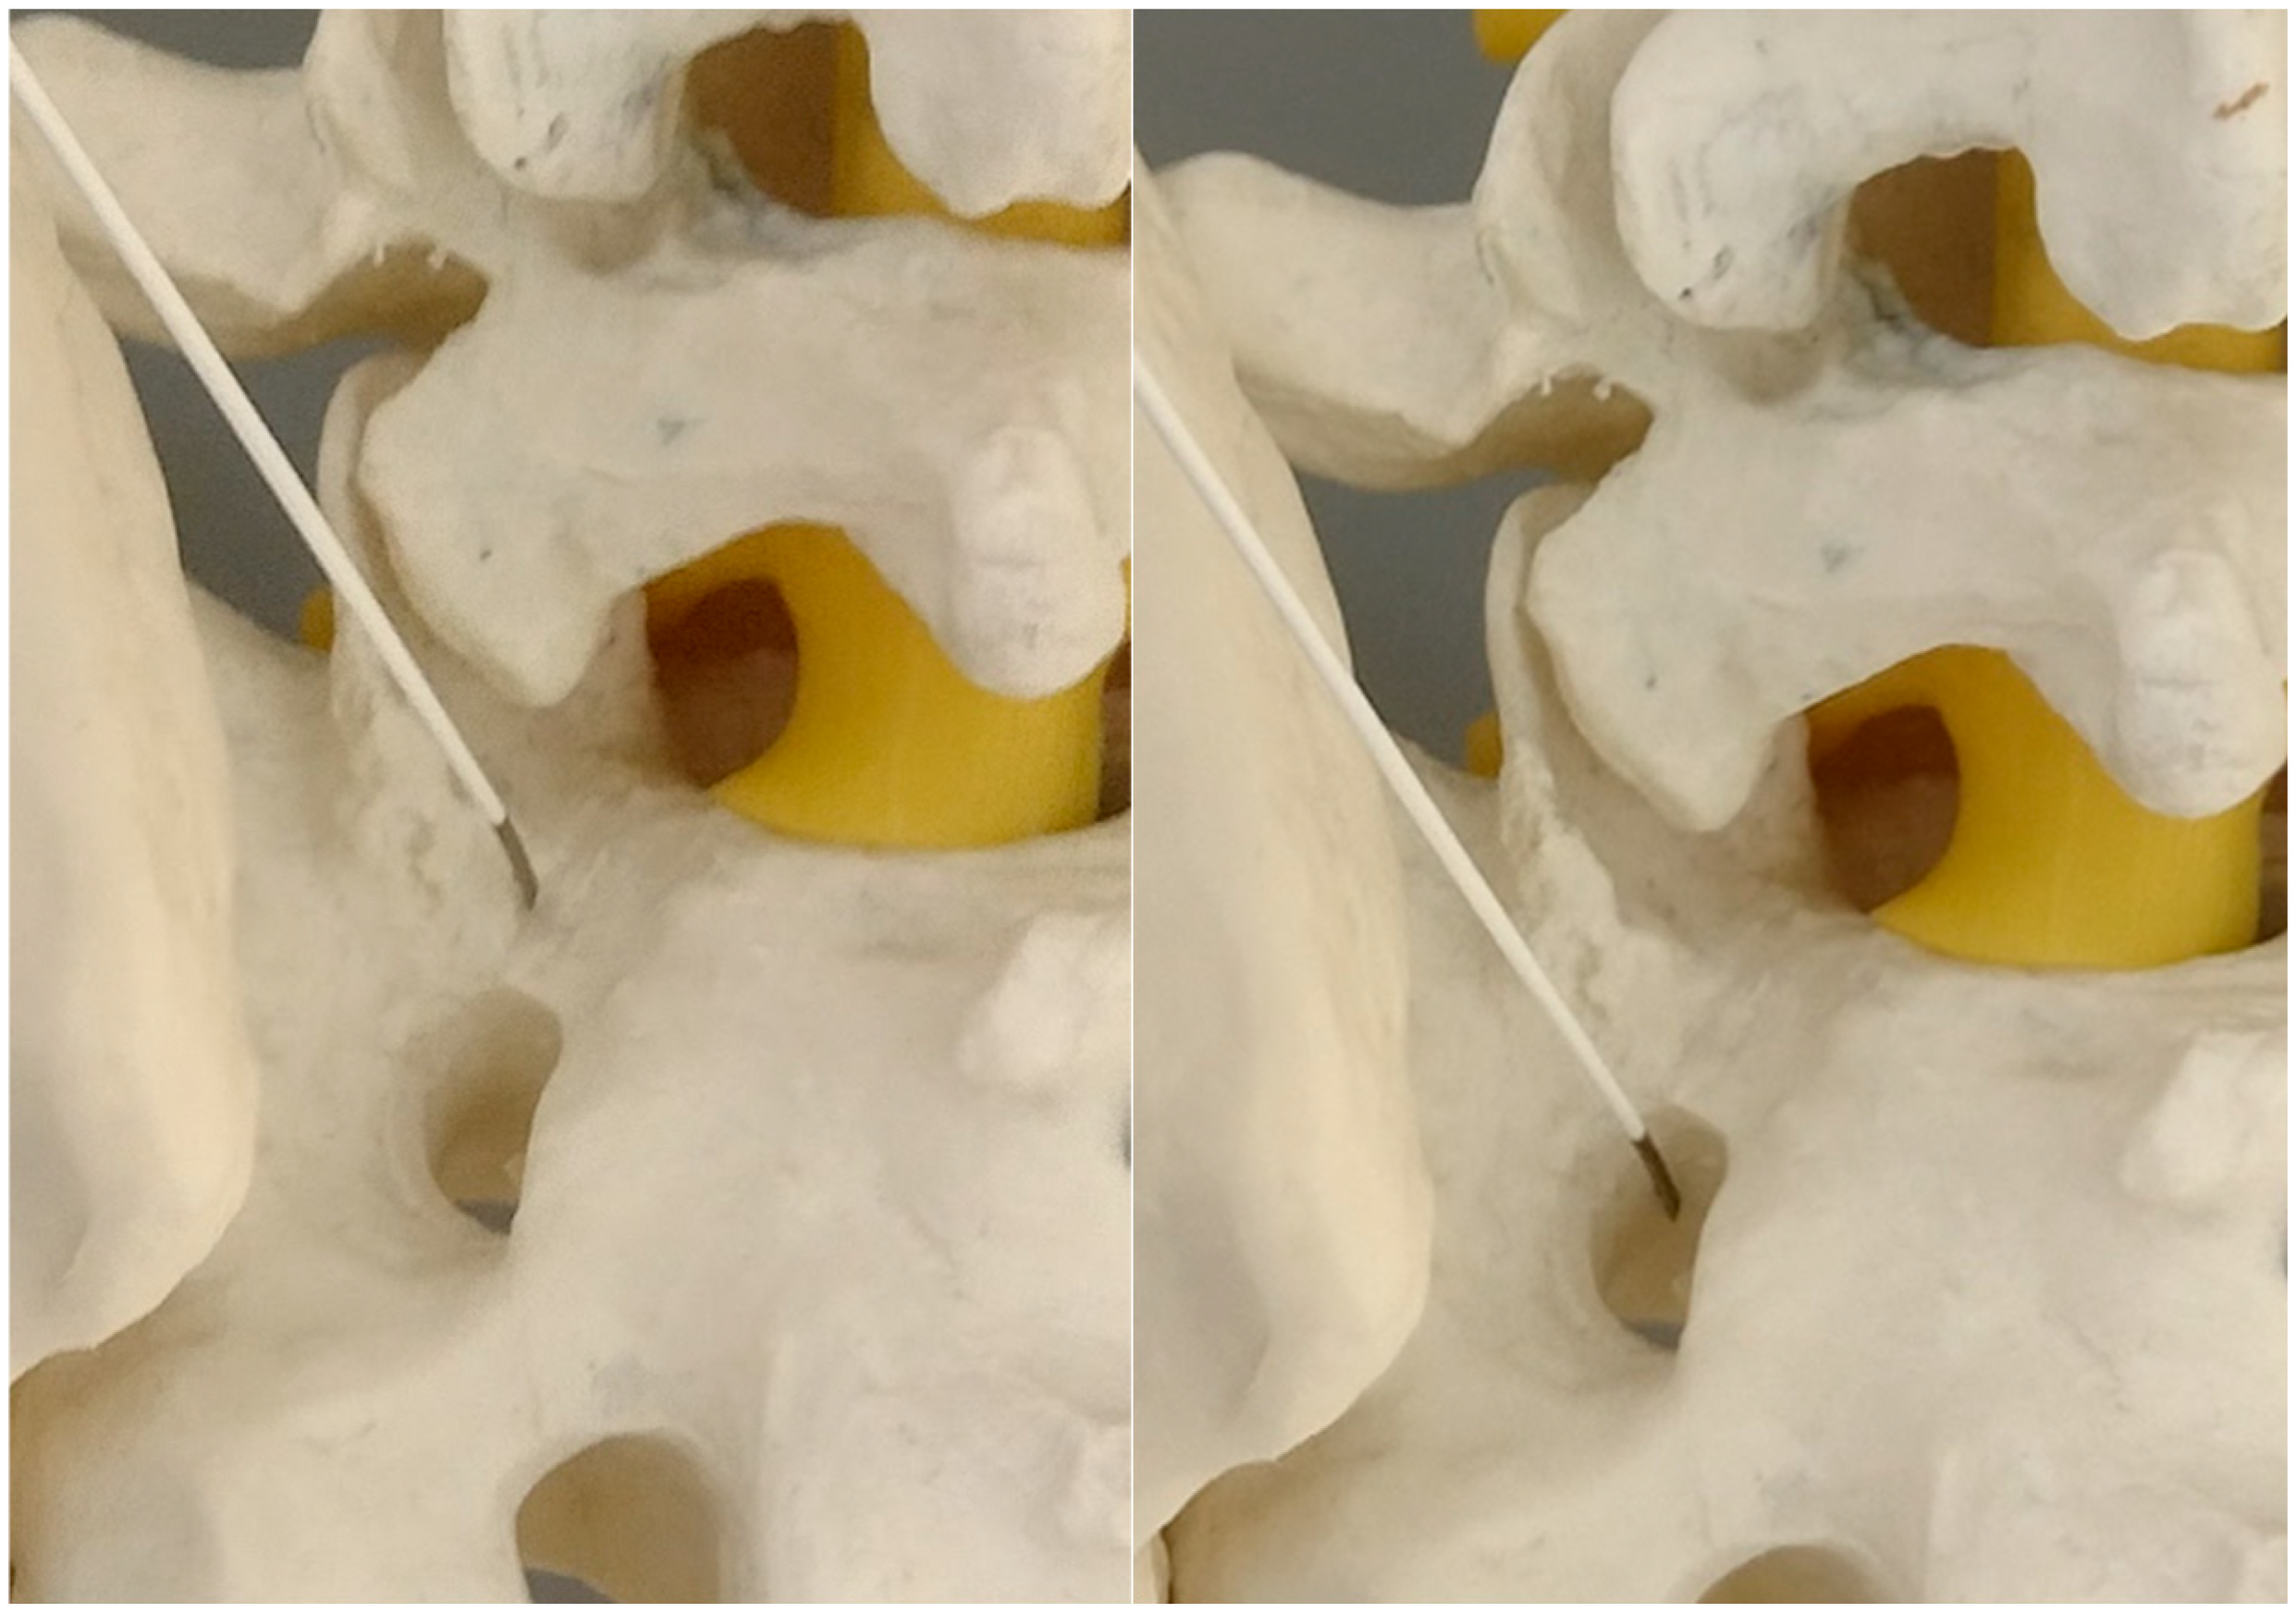

Figure 3. The primary target point—an inferior part of the facet (a model).

2.5. Primary Target Point

The primary target point for the needle introduction is the lower part of the facet joint or the caudal part of the articular surface of the S1 superior facet (Figure 2 and Figure 3).

It is safer to aim at the lower part of the facet joint, because it is an easily identifiable structure in any anatomical variation.

The use of a needle with a tilted end is the most convenient for the procedure. It enables the trajectory modification without the need for withdraw, while twisting the tip in the desired direction (allows for the slight modification of the tip orientation while the needle is advanced). The size of the needle is usually 20G through 18G, depending on the type of the procedure, although we prefer the larger size as it provides better control over the direction.

The trajectory is similar as in the approach of the lateral ramus of the posterior branch innervating the caudal part of the facet joint. Actually, a neurolesion of this branch could be performed as the first part of the procedure.

The needle is advanced toward the lower part of the L5/S1 facet joint. After the bony tissue’s contact with the gentle tapping of the needle the “soft over bony structure” of the capsule may be identified. This tapping can be utilized for the gentle anesthesia of the region, with a small amount of lidocaine, as further tapping of the bone will be performed.